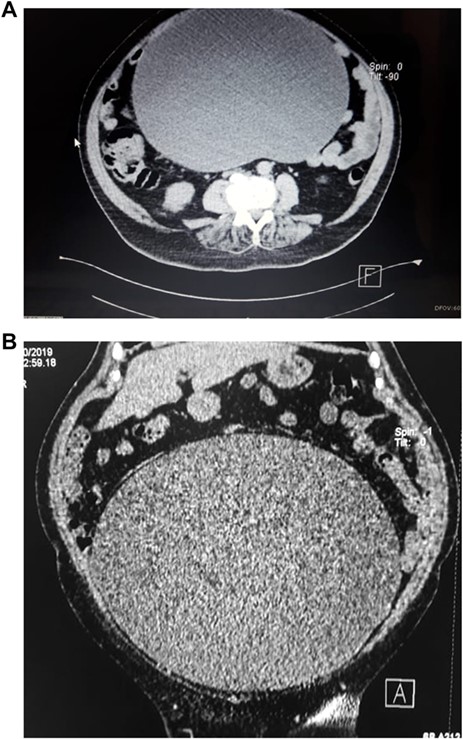

Upon examination, her abdomen was markedly distended; however, bowel sounds were normal and she did not have any abdominal discomfort. An abdominal echography revealed a giant heterogeneous mass with a thick wall and areas of internal septation. Due to this, an abdominal contrast-enhanced computed tomography (CT) was requested, revealing a giant 18.4 × 31.2 × 25.9 cm cystic lesion (4, 8 HU); the mass extended from the pelvis all the way through her upper abdomen, was dependent from the right adnexa and was in intimate contact with the bowel and omentum; however, the mass did not invade them. No lymph nodes or other masses were detected. (Fig. 1A and B) Complementary exams including CA-125, CAE and HE4 were normal. Due to the size of the mass, surgery was decided. On laparotomy, no ascites were identified; nonetheless, a 30 × 25 × 18 abdominopelvic mass was found filling most of her lower abdomen, and it was completely attached to the omentum and right adnexa. It had a whitish color and was covered with dilated blood vessels (Fig. 2A and B). Although there were no findings of lymph node metastasis or dissemination in the peritoneal cavity, we could not rule out that the tumor was solely benign, borderline malignant or malignant. Therefore, complete excision of the mass, along with complete omentectomy, appendectomy and close follow–up, was decided.

(A) CT scan, show giant cystic mass. (B) CT scan, showing ovarian tumor filling the lower abdomen.